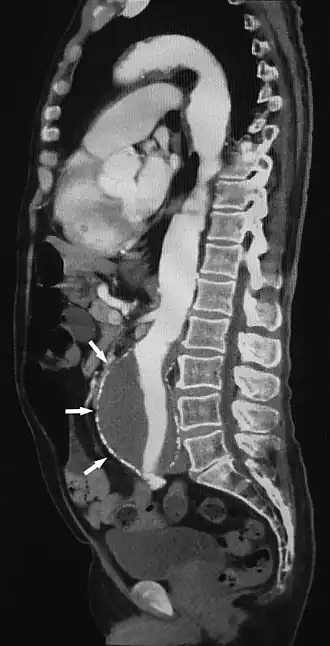

![]() Sagittal thin slice of a computed tomography angiography abdominal aortic aneurysm (AAA) (arrows) | |

CTA can be used in the chest and abdomen to identify aneurysms in the aorta or other major blood vessels. These areas of weakened blood vessel walls that bulge out can life-threatening if they rupture. CTA is the test of choice when assessing aneurysm before and after endovascular stenting due to the ability to detect calcium within the wall.[3] Another positive of CTA in abdominal aortic aneurysm assessment is that it allows for better estimation of blood vessel dilation and can better detect blood clots compared to standard angiography.[4]